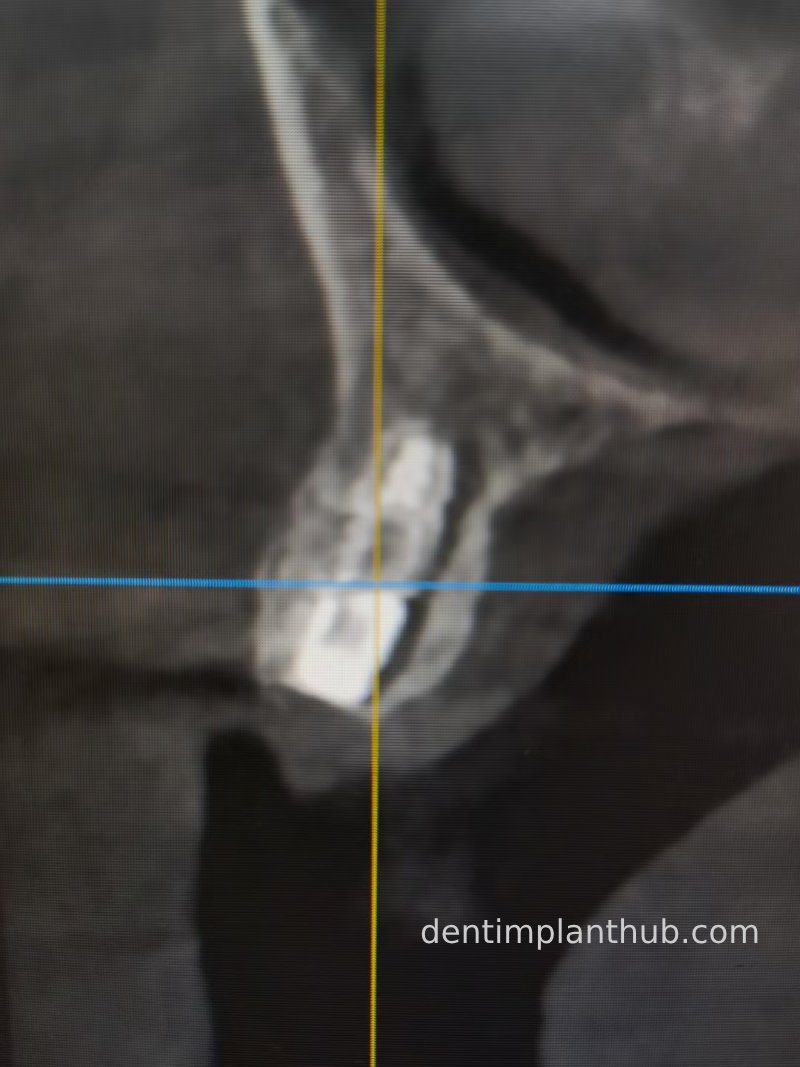

Three-dimensional CT images after surgery

23 Postoperative CT screenshot